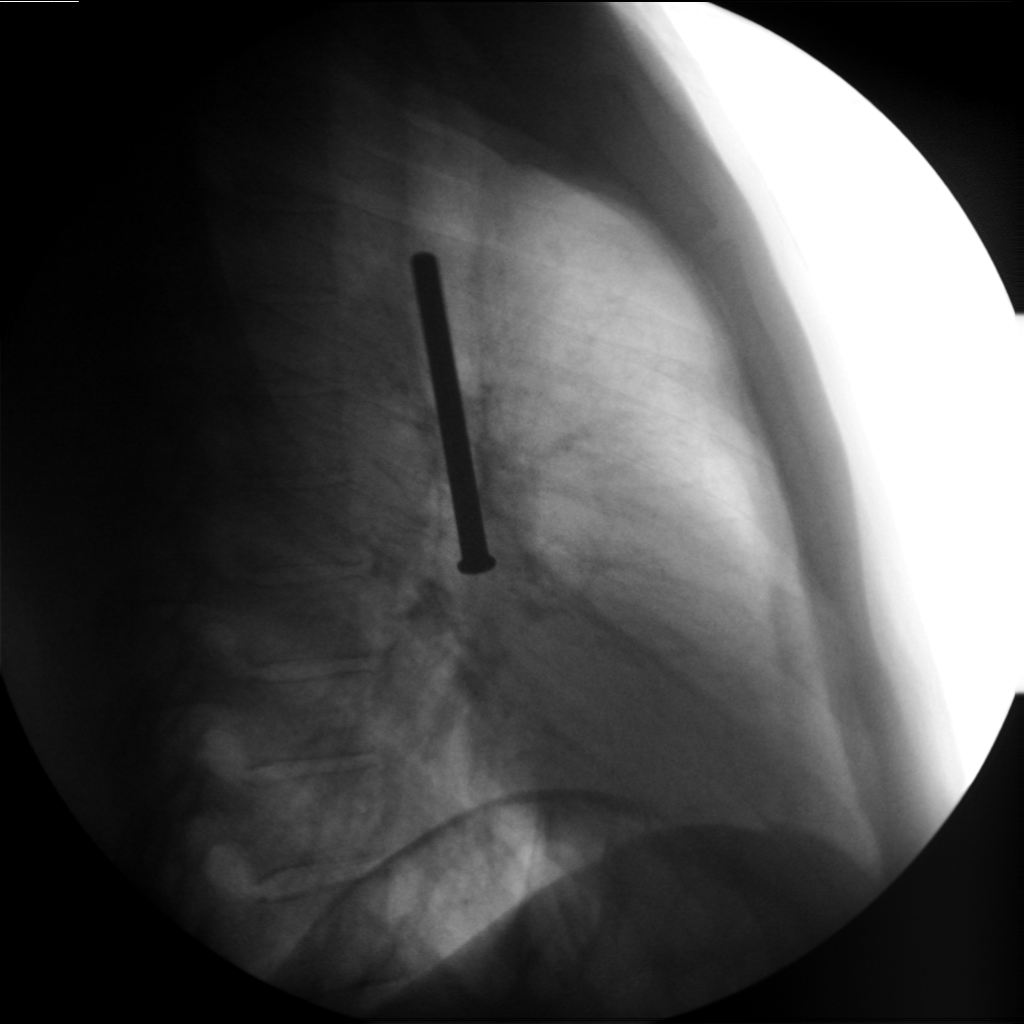

31 წლის პატიმარმა თვითდაზიანების მიზნით გადაყლაპა რამოდენიმე ნივთი, მათ შორის ერთი რკინის ნივთი გადასცდა, რის გამოც გაუძნელდა სუნთქვა, გაუჩნდა სტრიდორი, ძლიერი ტკივილი მარჯვენა გვერდში მოძრაობის დროს. საციცოცხლო ჩვენებით, ზოგადი გაუტკივარების პირობებში ჩატარდა რიგიდული ბრონქოსკოპია. გამოყენებული იყო ყველაზე დიდი ზომის ტუბუსი №13. ამოღების პროცესს ართულებდა უცხო სხეულის დიდი ზომა (სიგრძეში 10სმ). რამოდენიმე წარუმატებელი მცდელობის ბოლოს მოხერხდა უცხო სხეულის ექსტრაქცია. მანიპულაცია ჩატარდა გართულებების გარეშე.

- უცხო სხეული გვერდით პროექციაში